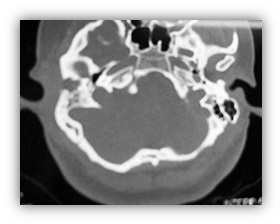

A la exploración se encuentra pabellón auricular derecho de tamaño pequeño, con alteración de su morfología, en área retroauricular se observa fístula con salida de material purulento, color amarillento, fétido, espeso. A la otoscopia se observa conducto auditivo externo estenótico, con presencia de material blanquecino-amarillo, fétido, de consistencia espesa, que obstruye el 100% de la luz (Imagen 1).

Tomografía simple de oídos con cortes axiales y coronales, en donde se observan celdillas mastoideas derechas poco desarrolladas, no neumatizadas; conducto auditivo sin desarrollo. No se observa adecuadamente la cadena osicular; material isodenso a tejidos blandos, que ocupa el epi-meso-hipotímpano; con resorción del scutum ipsilateral (Imagen 2 e Imagen 3).

Imagen 2: TC simple de oídos, corte axial; se observa atresia de conducto auditivo externo derecho.

Imagen 3: TC simple de oídos, corte coronal; se observa ocupación de epi-meso-hipotímpano por lesión isodensa a tejidos blandos.